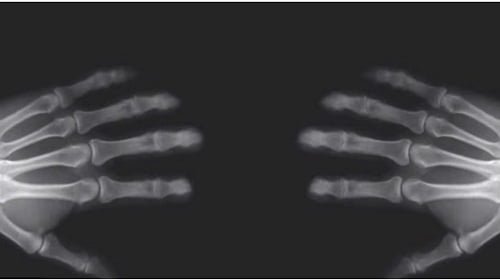

Bien que le fait d’étirer les articulations permet de stimuler les terminaisons nerveuses, l’habitude de se faire craquer les doigts peut entraîner des dommages au niveau du cartilage qui recouvre les articulations.

D’un point de vue scientifique, le fait de faire souvent craquer ses doigts pourrait endommager le cartilage que couvre l’articulation.